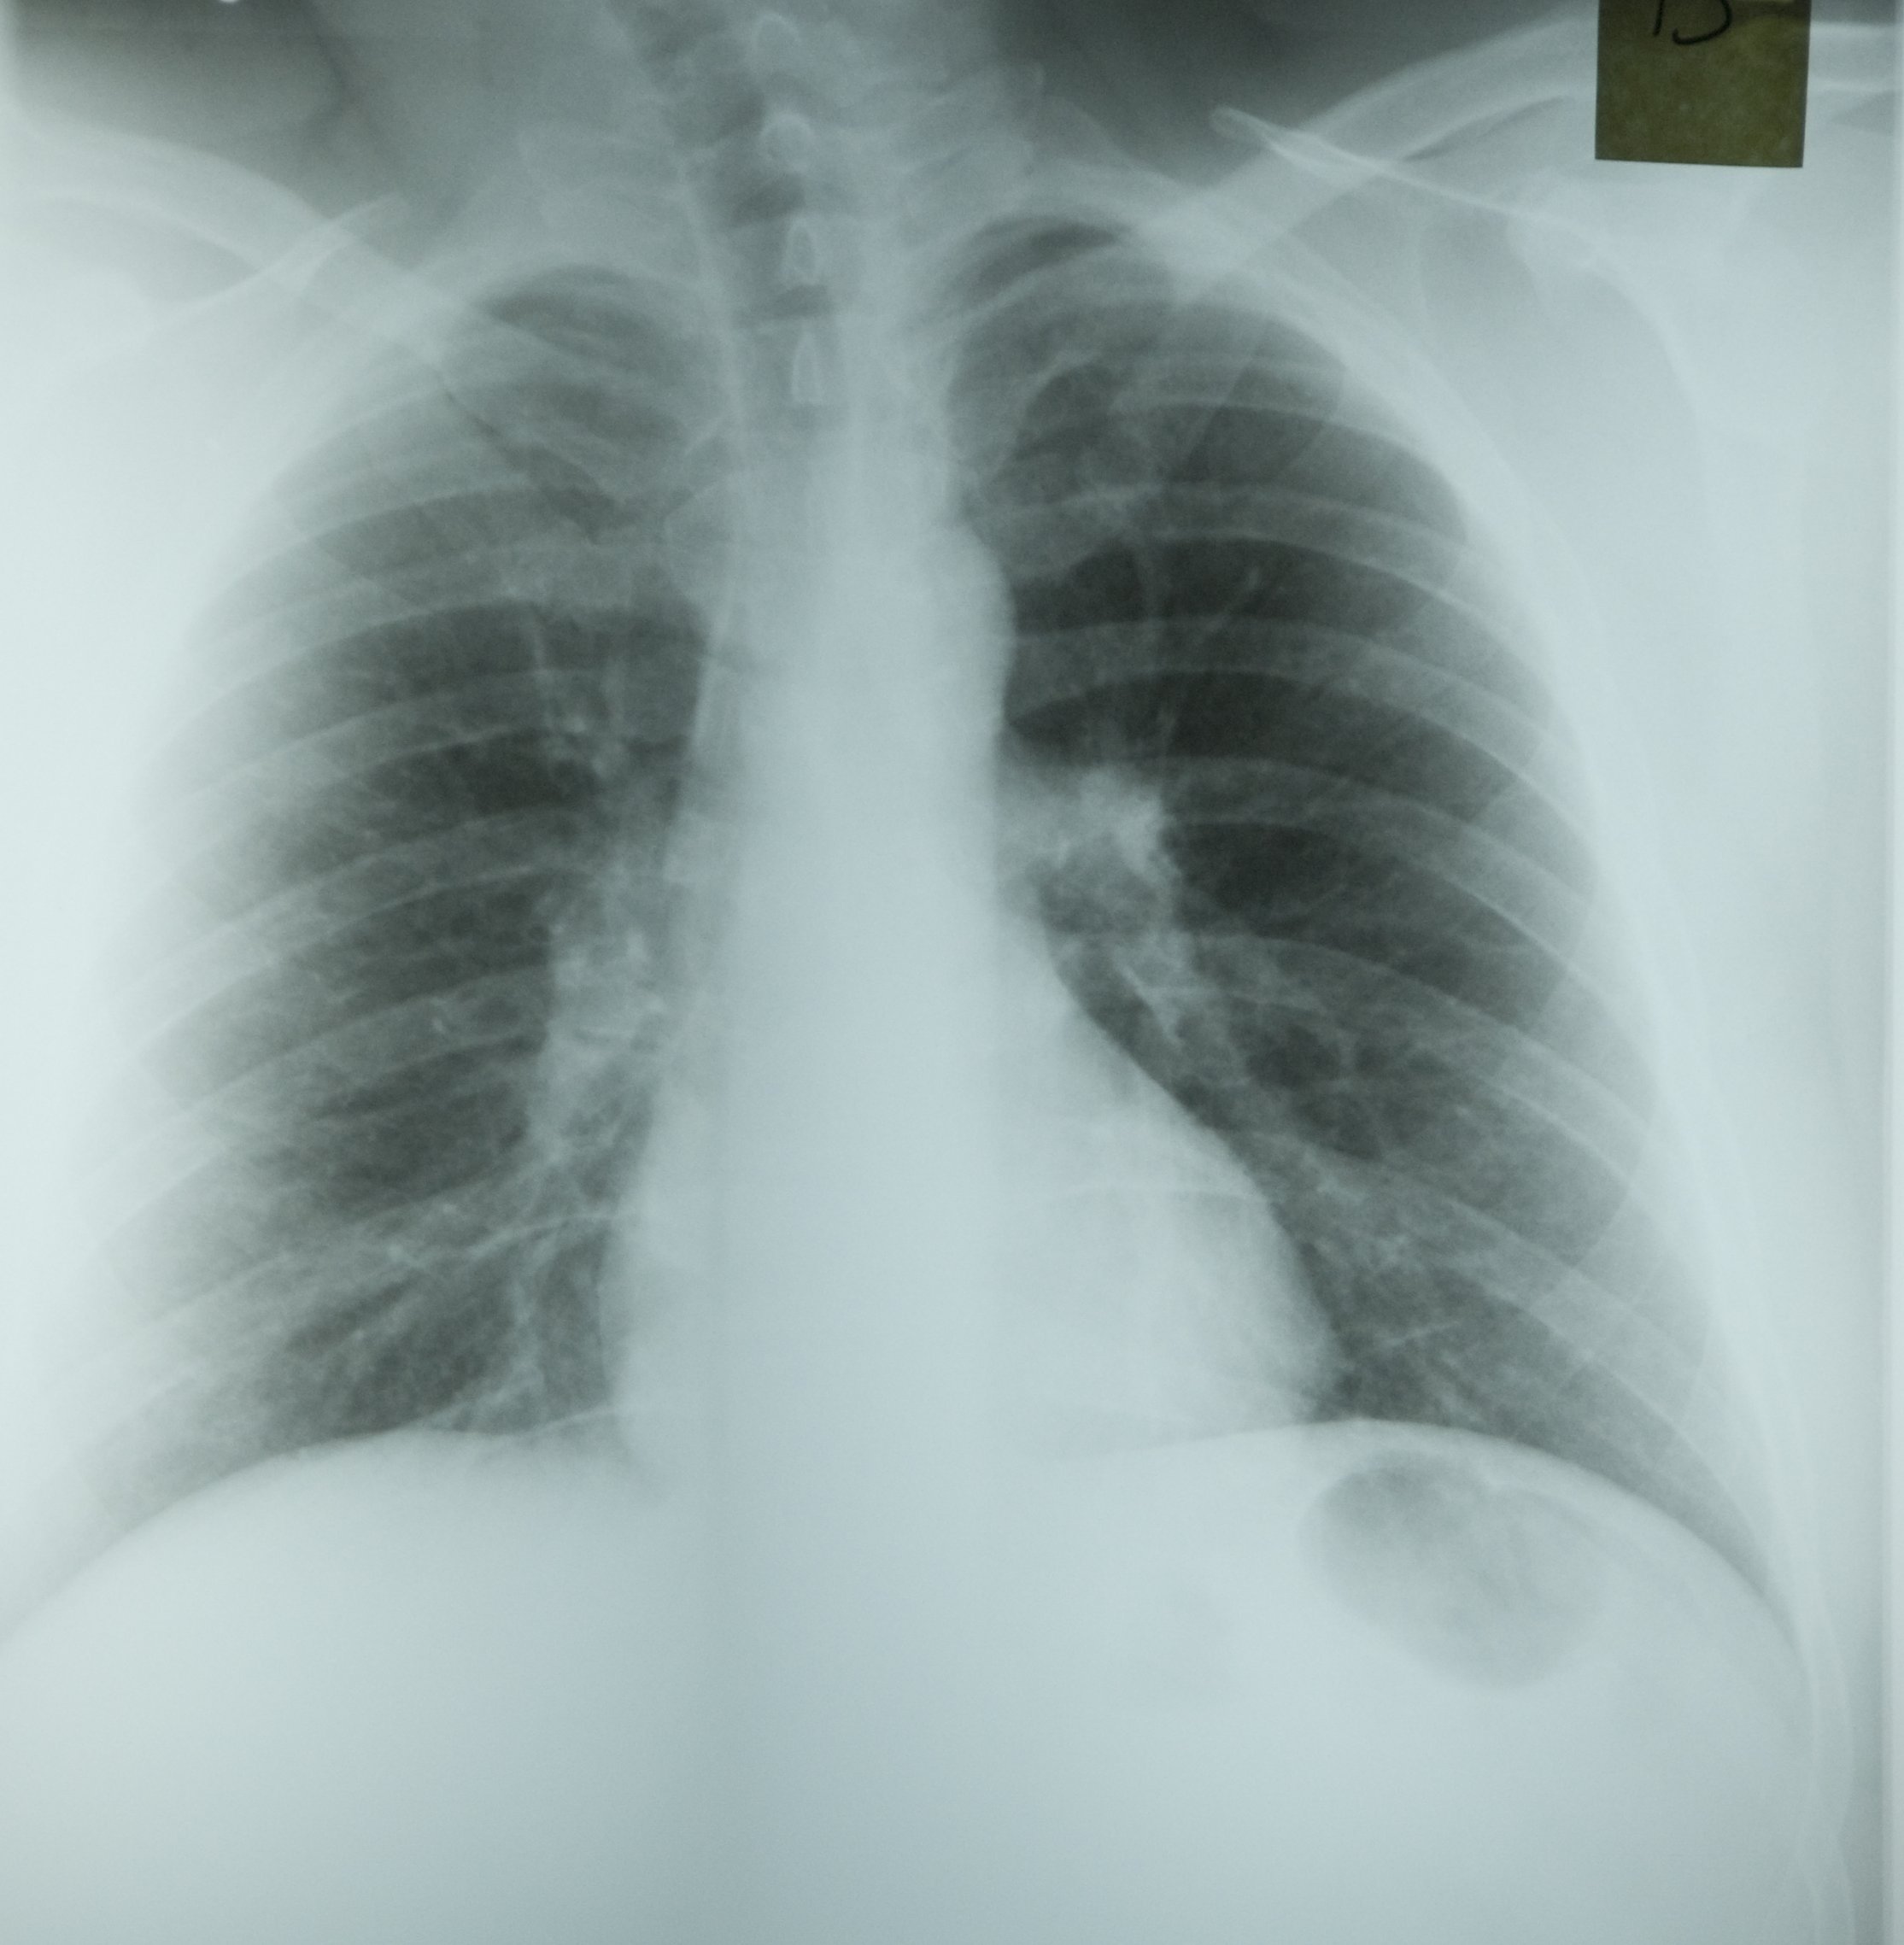

A chest radiograph was taken at that time (Figure 1.3).

Figure 1.3

Both coal and silica dust exposures trigger inflammation of the airways and the interstitium, and pneumoconiosis can continue to progress for years after termination of all dust exposure (1). This is one reason why primary prevention through dust control is critical. Inflammatory nodules can coalesce to form PMF (also called complicated pneumoconiosis), which is recognized on the chest radiograph as one or more lesions 10mm in diameter or greater. After PMF develops, the fibrosis and associated emphysema often progress even without further dust exposure, as was the case with this patient. Adjacent lung parenchyma is pulled towards the lesions, which most typically occur in the upper lung. The large airways are distorted as lung volume is lost and lung function may show obstructive and/or restrictive impairments.